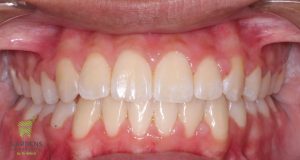

Initial and Final photos correcting a deep bite